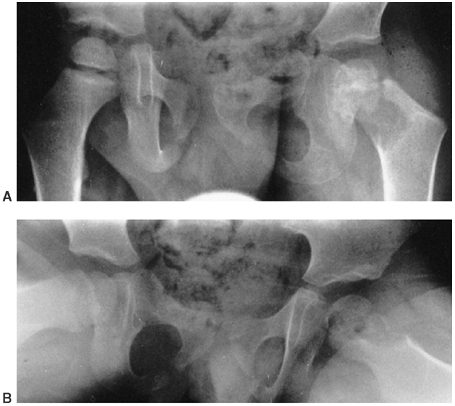

![]() |

Figure 13.5 Magnetic resonance imaging (MRI) may be very helpful when differentiating between osteomyelitis and primary bone malignancy. A, B:

This 12-year-old female patient was referred for evaluation of femoral osteosarcoma. The standard anteroposterior and lateral radiograph shows periosteal reaction along the distal one third of the femur, consistent with primary bone sarcoma or osteomyelitis (arrows). C: T2-weighted MRI without contrast demonstrates preservation of some normal marrow fat within the intramedullary canal and a fluid-filled abscess cavity diagnostic of osteomyelitis. Diffuse inflammation is present in adjacent soft tissues without a discrete solid mass. Osteomyelitis was confirmed at surgery. |